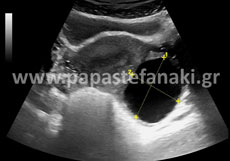

Υπερηχογράφημα Κάτω Κοιλίας - Ελάσσονος Πυέλου - Έσω Γεννητικών Οργάνων

Με το υπερηχογράφημα αυτό ελέγχουμε τα όργανα της κάτω κοιλίας και κύρια την ουροδόχο κύστη, την μήτρα και τις ωοθήκες στις γυναίκες και τον προστάτη στους άνδρες .

Προετοιμασία ασθενούς είναι απαραίτητη.

Έτσι 2 ώρες πριν την εξέταση πρέπει να πάρετε 5– 6 ποτήρια υγρών (νερό, χυμό μη ανθρακούχο κλπ) ώστε να γεμίσει η ουροδόχος κύστη (άρα δεν πρέπει να ουρήσετε πριν την εξέταση).

Δεν πρέπει να έχει προηγηθεί την ίδια ημέρα γαστροσκόπηση, ορθοσκόπηση, εξέταση στομάχου ή εντέρου.